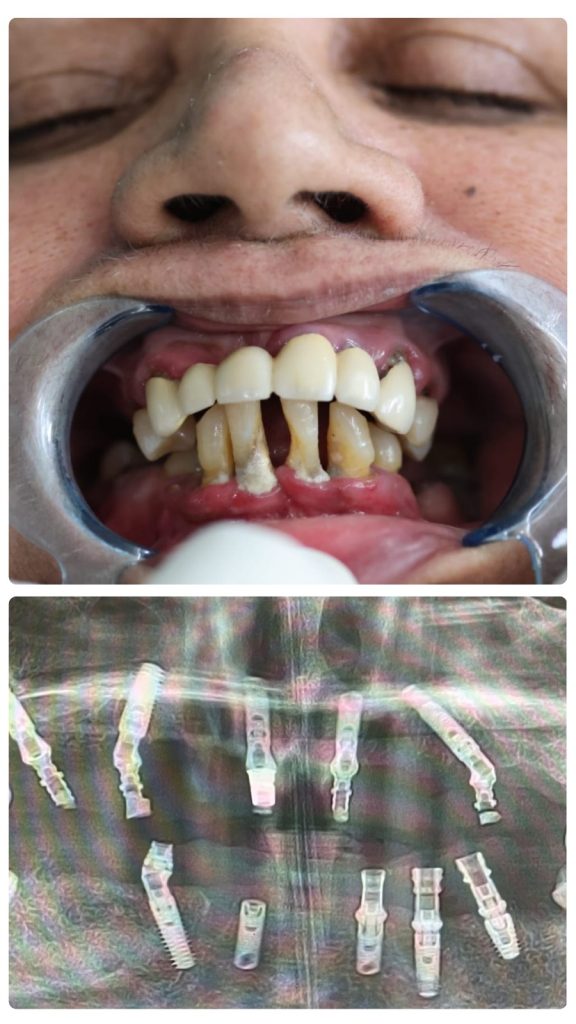

Best Dental Implant Clinics in Chandigarh - Dr. Vandna's 12 Implant Journey

Before

AFTER

I was facing very serious problems with my teeth, to the point where I struggled to eat properly and felt constantly self-conscious while talking. I had visited many other clinics previously, but unfortunately, they all failed to provide a lasting solution.

Thankfully, someone I know suggested Elite Dental & Implant Clinic, telling me they are known as one of the best dental implant clinics in chandigarh. I decided to visit, and I am so glad I did. I got 12 implants done here, and I can confidently say that Dr. Gaurav Ahuja is indeed the best dentist in chandigarh.

Dr. Gaurav created the perfect environment and made me feel completely comfortable. The clinic was super hygienic, and the staff was very friendly; they took such perfect care of me that I didn’t feel any stress at all. What impressed me most was that even after the treatment, they always contacted me to ask if I was feeling well or experiencing any discomfort. Their dedication to patient care is truly outstanding.

– Dr. Vandna